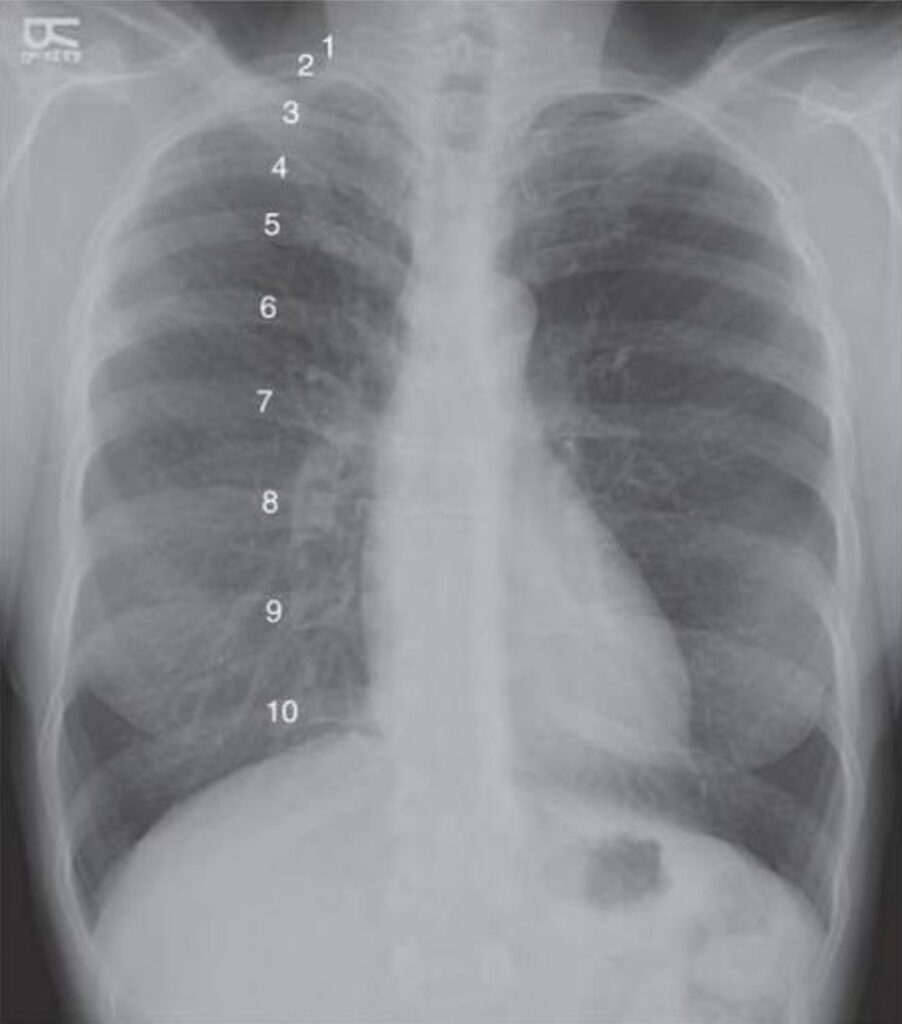

La forma más práctica y objetiva de estimar la inspiración en una radiografía torácica frontal consiste en contar el número de costillas posteriores visibles por encima del diafragma. Las costillas posteriores se identifican con mayor facilidad que las anteriores debido a su orientación casi horizontal y a su unión directa con los cuerpos vertebrales dorsales. En la proyección frontal, estas costillas se aprecian como arcos relativamente rectilíneos que se extienden lateralmente desde la columna vertebral. En contraste, las costillas anteriores descienden en dirección inferomedial hacia el esternón y presentan una inclinación oblicua hacia los pies. Además, su porción cartilaginosa anterior no suele visualizarse en individuos jóvenes, dado que el cartílago costal es radiolúcido y solo se hace visible cuando experimenta calcificación con el envejecimiento.

En condiciones ideales, la visualización de diez costillas posteriores por encima del hemidiafragma derecho se considera indicativa de una inspiración excelente. Este parámetro sugiere que el paciente realizó una inspiración profunda adecuada y que el volumen pulmonar alcanzado permite una evaluación confiable de la arquitectura pulmonar y de las siluetas cardiomediastínicas. Sin embargo, en el entorno hospitalario, donde muchos pacientes presentan dolor, debilidad, compromiso neurológico o limitaciones mecánicas para cooperar con la maniobra respiratoria, la visualización de ocho a nueve costillas posteriores suele considerarse suficiente para una interpretación diagnóstica razonable. Valores inferiores a este umbral deben alertar al intérprete sobre la posibilidad de inspiración insuficiente y, por tanto, sobre el riesgo de artefactos.